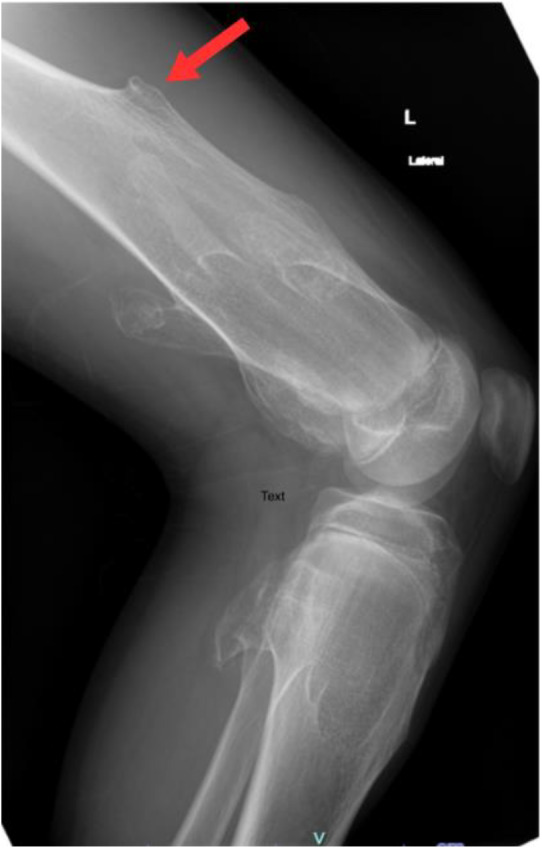

Exostosis, or osteochondroma, is an irregular bone growth commonly occurring near the femur, scapula, humerus and ribs. It can be a single isolated lesion or multiple lesions as in hereditary multiple exostoses (HME) which is a genetic autosomal dominant disorder. Although often asymptomatic, complications such as haemothorax are rare and have serious implications if not promptly recognised. We report a 15-year-old male patient who presented to a tertiary care hospital in Muscat, Oman, in 2023 who presented with progressive chest pain and dyspnoea. The patient had a family history of HME. Video-assisted thoracoscopic surgery (VATS) confirmed the osteochondromatous lesions on the 8th rib, which was causing the haemothorax. The lesion was resected and post-surgery, the symptoms resolved. No recurrence was documented up to the time of writing this report.